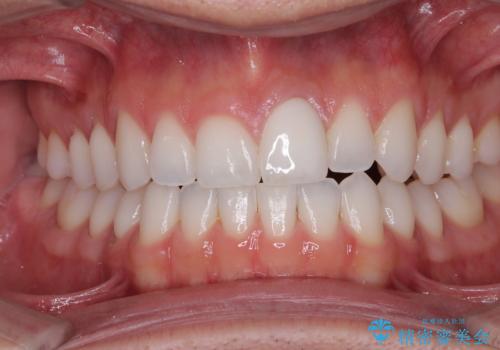

ぶつけて変色した前歯 オールセラミッククラウン治療

- 以前ぶつけて神経を取り除いてから、徐々に変色してきた前歯が気になるとのことで来院された患者様です。

神経を取り除いた歯の変色はホワイトニングでは十分に改善できないため、オールセラミッククラウンにて補綴治療を行うこととしました。

定期的にホワイトニングをされていることや、前歯の歯列が左右非対称であることから、色合いや形態の修正が多くなることが予想されたため、オーダーメイドタイプのグレードを選択していただき、治療を進めて行くこととしました。

予想通り色と形の修正が多く必要となりましたが、最終的には納得のいく仕上がりとなりました。